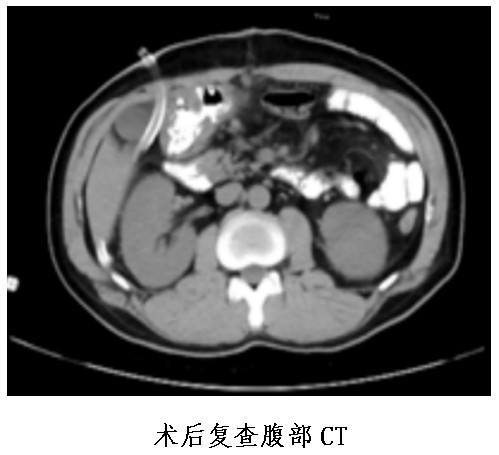

患者因體檢時發(fā)現(xiàn)肝功能異常后到市中心醫(yī)院消化內(nèi)科住院,進行腹部CT發(fā)現(xiàn)胃底及胃體小彎側(cè)局部胃壁結(jié)節(jié)樣增厚、伴胃小網(wǎng)膜囊內(nèi)多發(fā)稍大淋巴結(jié)。超聲胃鏡檢查發(fā)現(xiàn)胃部有多發(fā)隆起病變。病理檢查結(jié)果提示為神經(jīng)內(nèi)分泌瘤。為尋求手術(shù)治療,患者于1月4日轉(zhuǎn)入胃腸外科。

普外中心主任兼胃腸外科主任譚曙光組織醫(yī)師團隊就患者治療方案進行討論,認為該名胃體神經(jīng)內(nèi)分泌瘤患者,符合手術(shù)指征。經(jīng)過反復(fù)評估并與患者本人及家屬溝通,最終譚曙光醫(yī)師團隊決定摒棄傳統(tǒng)的胃切除術(shù),選擇腹腔鏡根治性近端胃切除+D2淋巴結(jié)清掃及雙通道吻合(食道空腸over-Lap吻合及空腸遠端胃吻合)術(shù),有效減少了反流性食道炎等術(shù)后并發(fā)癥的發(fā)生。1月9日,患者完成了手術(shù),術(shù)后恢復(fù)順利并于22日出院。